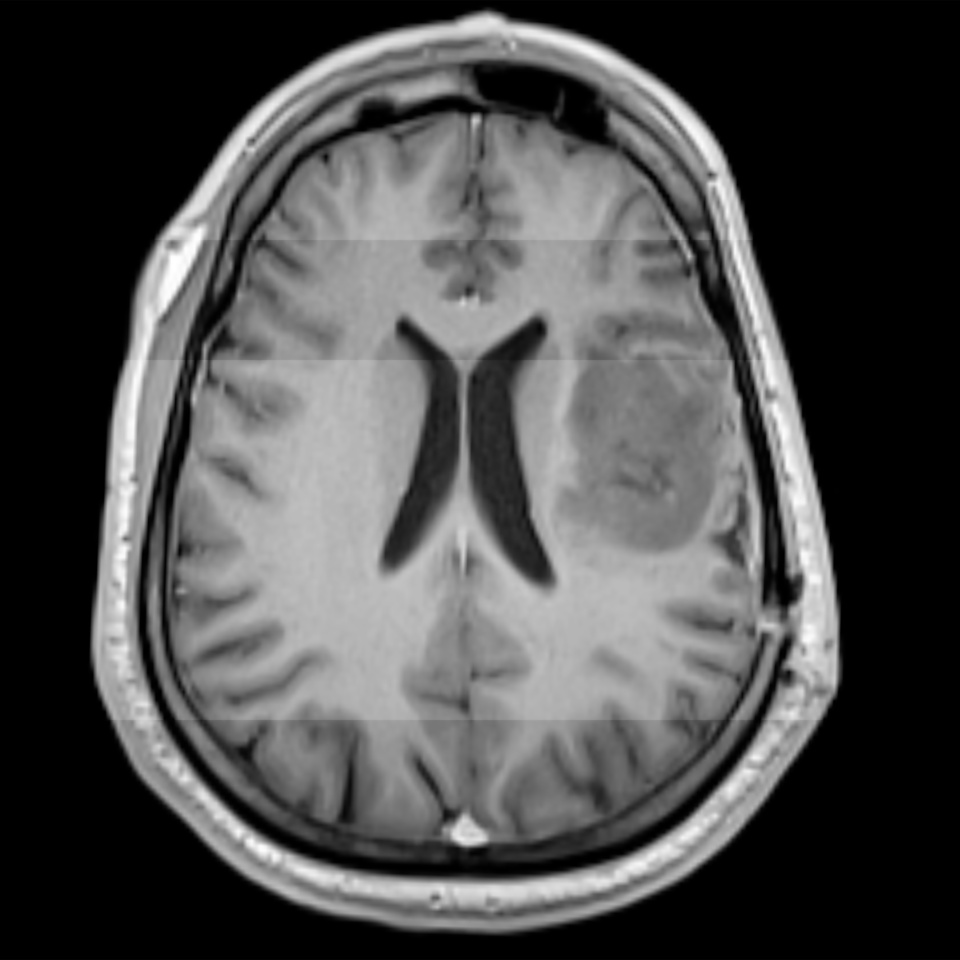

Diagnosing Brain Tumors with Advanced Neuroimaging

Accurate diagnosis is critical in managing brain tumors such as astrocytomas and oligodendrogliomas. Advanced neuroimaging techniques, including MRI and CT scans, are essential for proper staging and planning of interventions. Our practice in Los Angeles integrates these technologies into our diagnostic protocols, ensuring that we develop effective treatment strategies based on precise imaging data. Dr. Cohen Gadol’s expertise allows us to interpret these findings accurately, improving the care we deliver. His background in engineering, clinical research, and surgical innovation enhances our diagnostic and treatment planning capabilities.